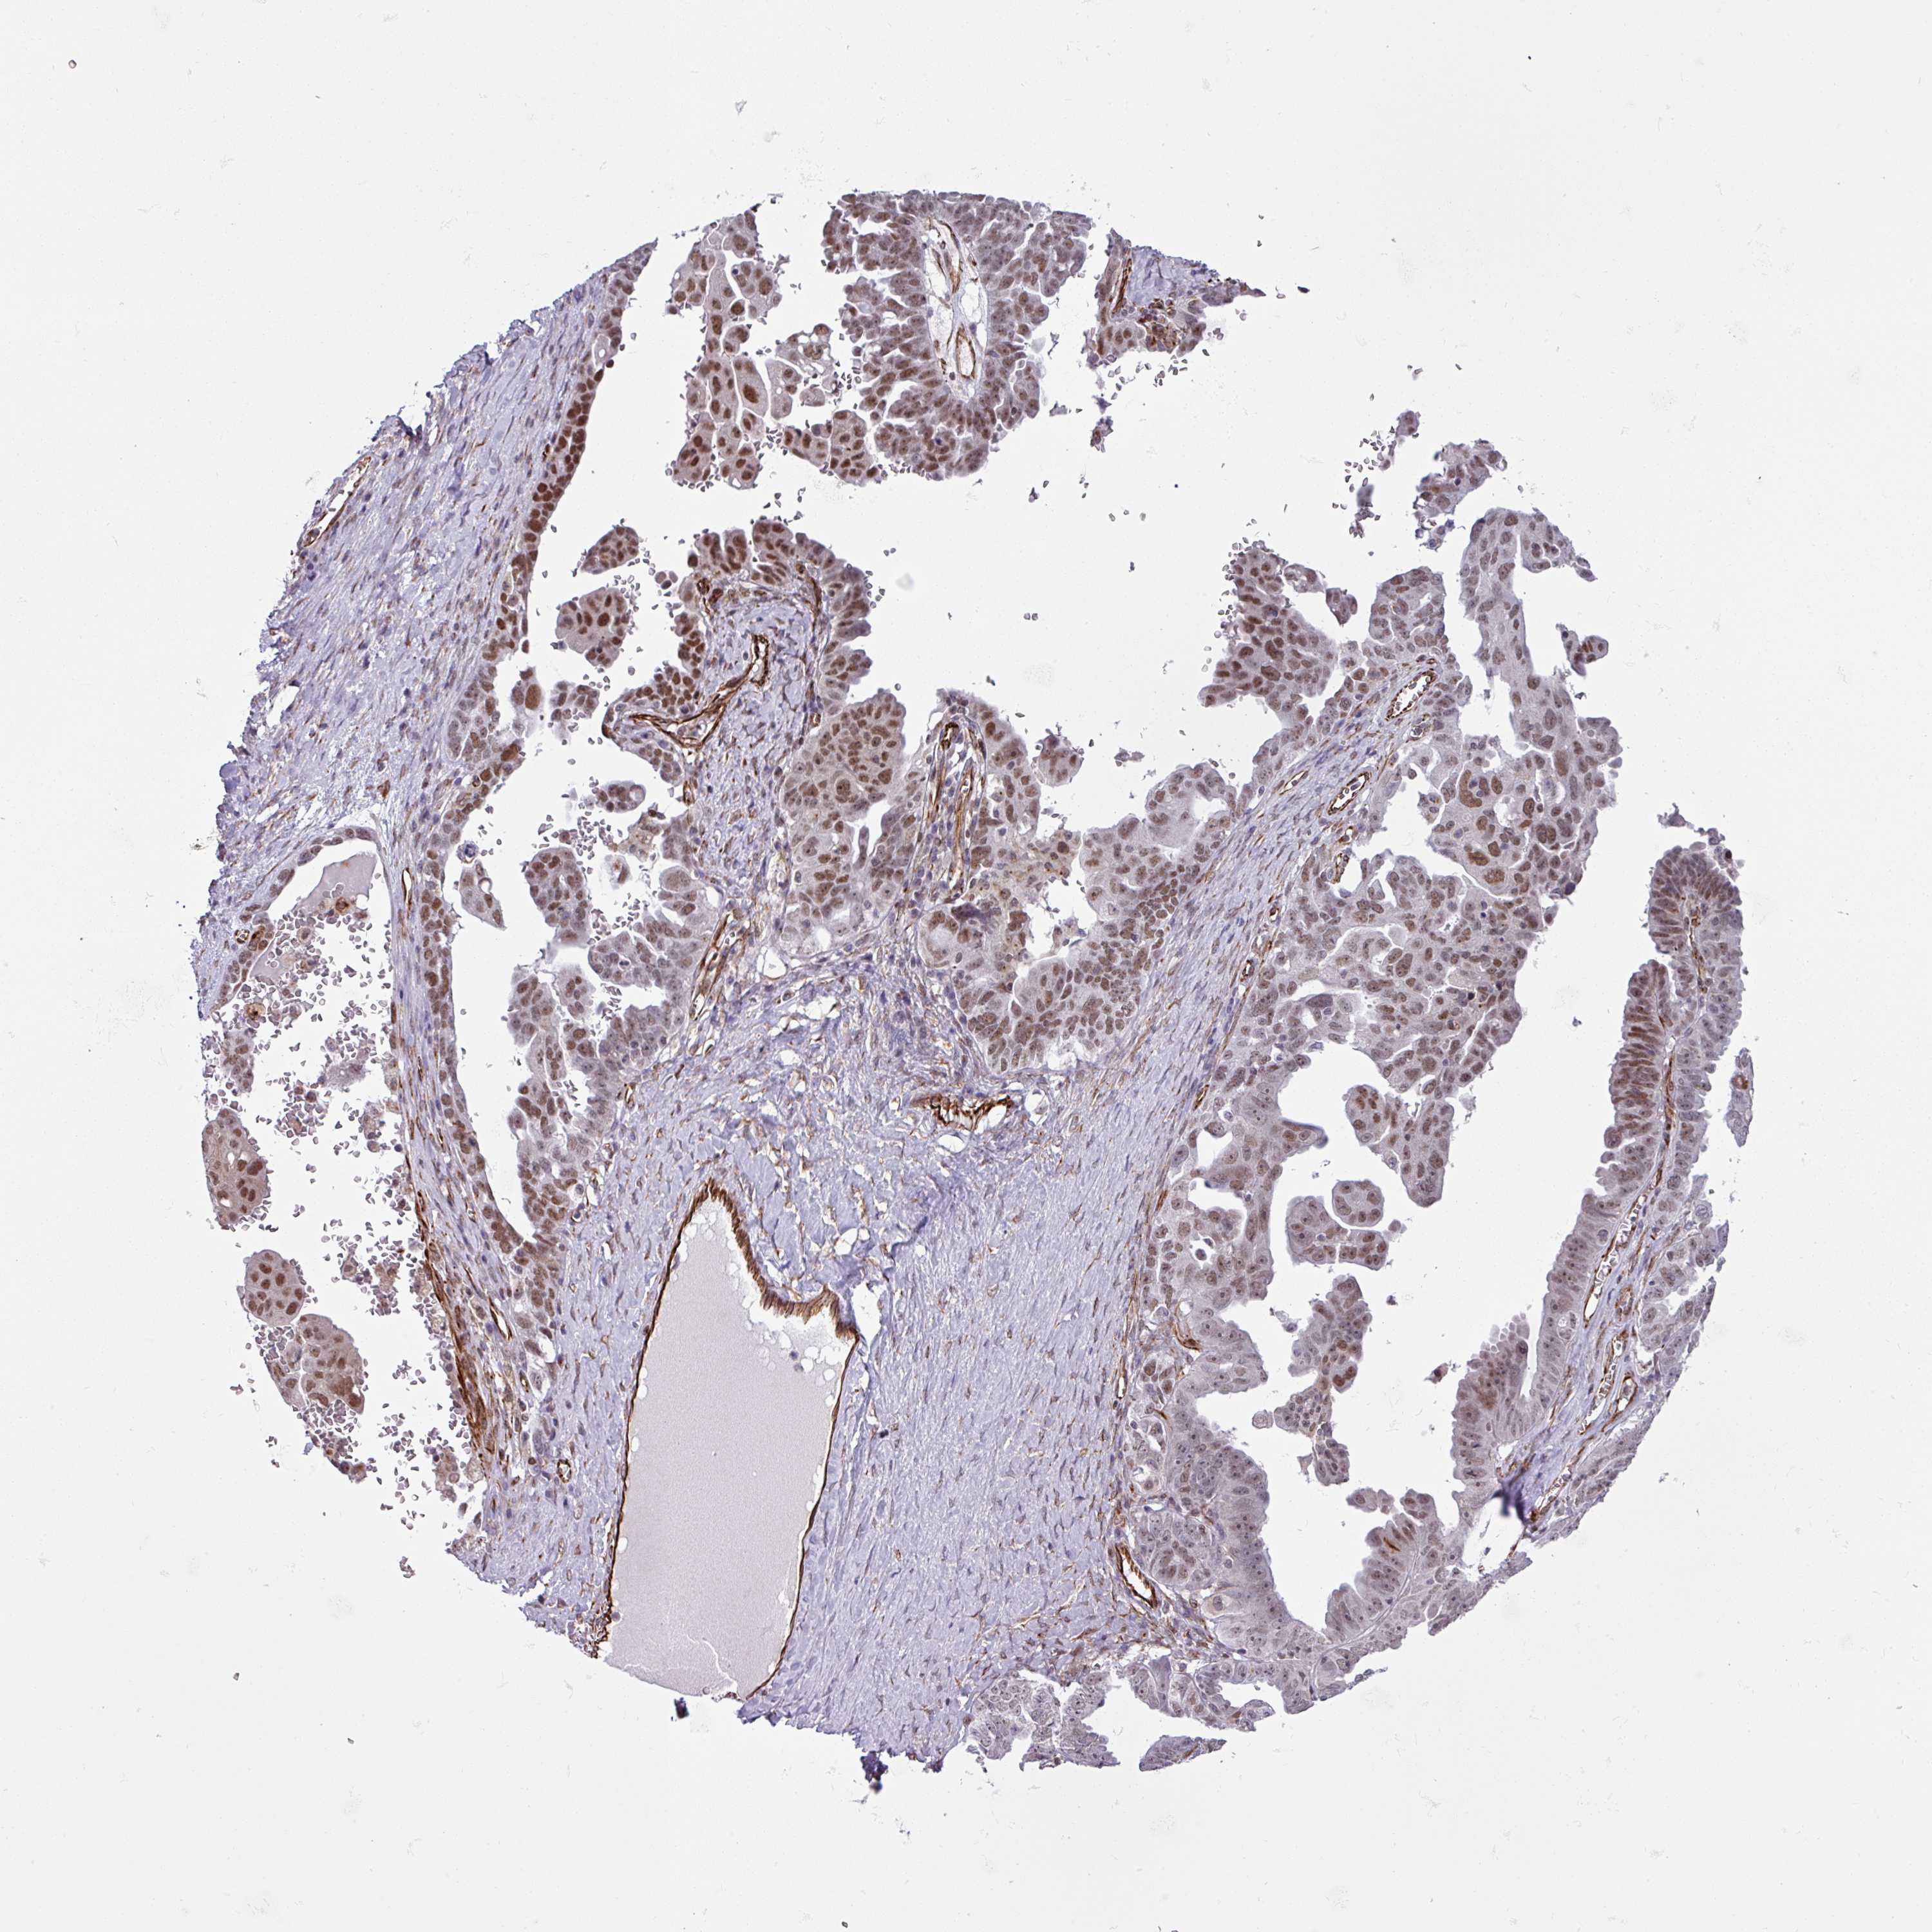

OVARIAN CANCER - Protein expressioni

A mouse-over function shows sample information and annotation data. Click on an image to view it in a full screen mode. Samples can be filtered based on level of antibody staining by selecting one or several of the following categories: high, medium, low and not detected. The assay and annotation is described here.

Note that samples used for immunohistochemistry by the Human Protein Atlas do not correspond to samples in the TCGA dataset.

Antibody stainingi

Antibody staining in the annotated cell types in the current human tissue is reported as not detected, low, medium, or high, based on conventional immunohistochemistry profiling in selected tissues. This score is based on the combination of the staining intensity and fraction of stained cells.

Each image is clickable and will lead to virtual microscopy that enables deeper exploration of all samples and also displays staining intensity scores, fraction scores and subcellular localization as well as patient and tissue information for each sample.

Antibody HPA043368

Staining

High

Medium

Low

Not detected

Intensity

Strong

Moderate

Weak

Negative

Quantity

>75%

75%-25%

<25%

None

Location

Nuclear

Cytoplasmic/membranous

Cytoplasmic/membranous,nuclear

Cystadenocarcinoma, serous, NOS

Carcinoma, endometroid

Cystadenocarcinoma, mucinous, NOS

Carcinoma, NOS